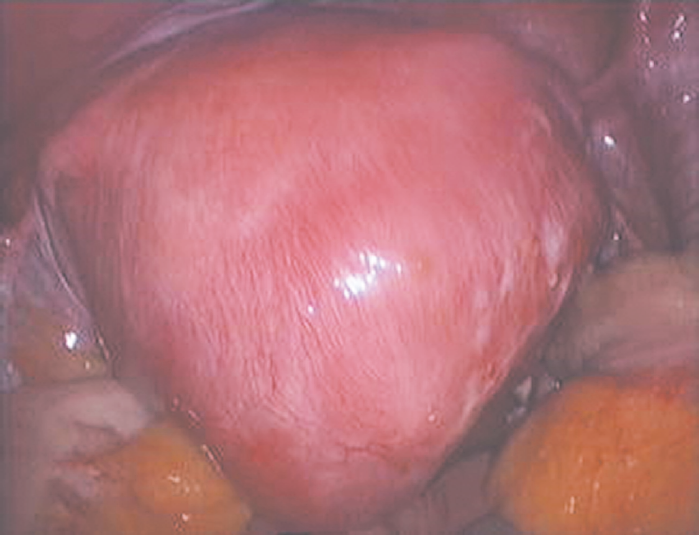

Авторы работы [5] полагают, что объем оперативного лечения лапароскопическим доступом зависит от формы аденомиоза. В частности, при кистозных и узловых формах у 100 % больных производилось удаление очагов поражения лапароскопическим доступом. У 89 % пациенток со склеротической формой лапароскопически выполнялось широкое удаление аномальной ткани (рис. 2). У 81 % больных с диффузной формой осуществлена лапароскопическая гистерэктомия.

Рис. 2. Лапароскопическая картина склеротической формы аденомиоза по G. Pistofidis et al., 2014 [5]

Fig. 2. Sclerotic type of adenomyosis identified during laparascopy (according to G. Pistofidis et al. [5])